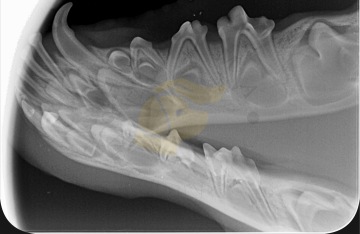

Intraorální rentgen – když zub není vidět

V případech, kdy některý zub není viditelný, ale není jasné, zda skutečně chybí, nebo je pouze neprořezaný, se používá intraorální rentgen. Tento typ snímkování umožňuje zjistit, zda se zub nachází v čelisti, ale z nějakého důvodu neprorazil dáseň (např. je impaktovaný nebo retenovaný).

Rentgen pomáhá určit:

Přítomnost zubu v čelisti.

Genetické chybění zubu (nezaložen).

Zda byl zub extrahován nebo ztracen v důsledku úrazu či nemoci.

Intraorální rentgen se provádí nejčastěji v sedaci nebo krátké anestezii, protože pes musí během zákroku zůstat zcela v klidu. Je to neinvazivní a velmi přesný způsob, jak doložit plnochrupost i v nejasných případech.